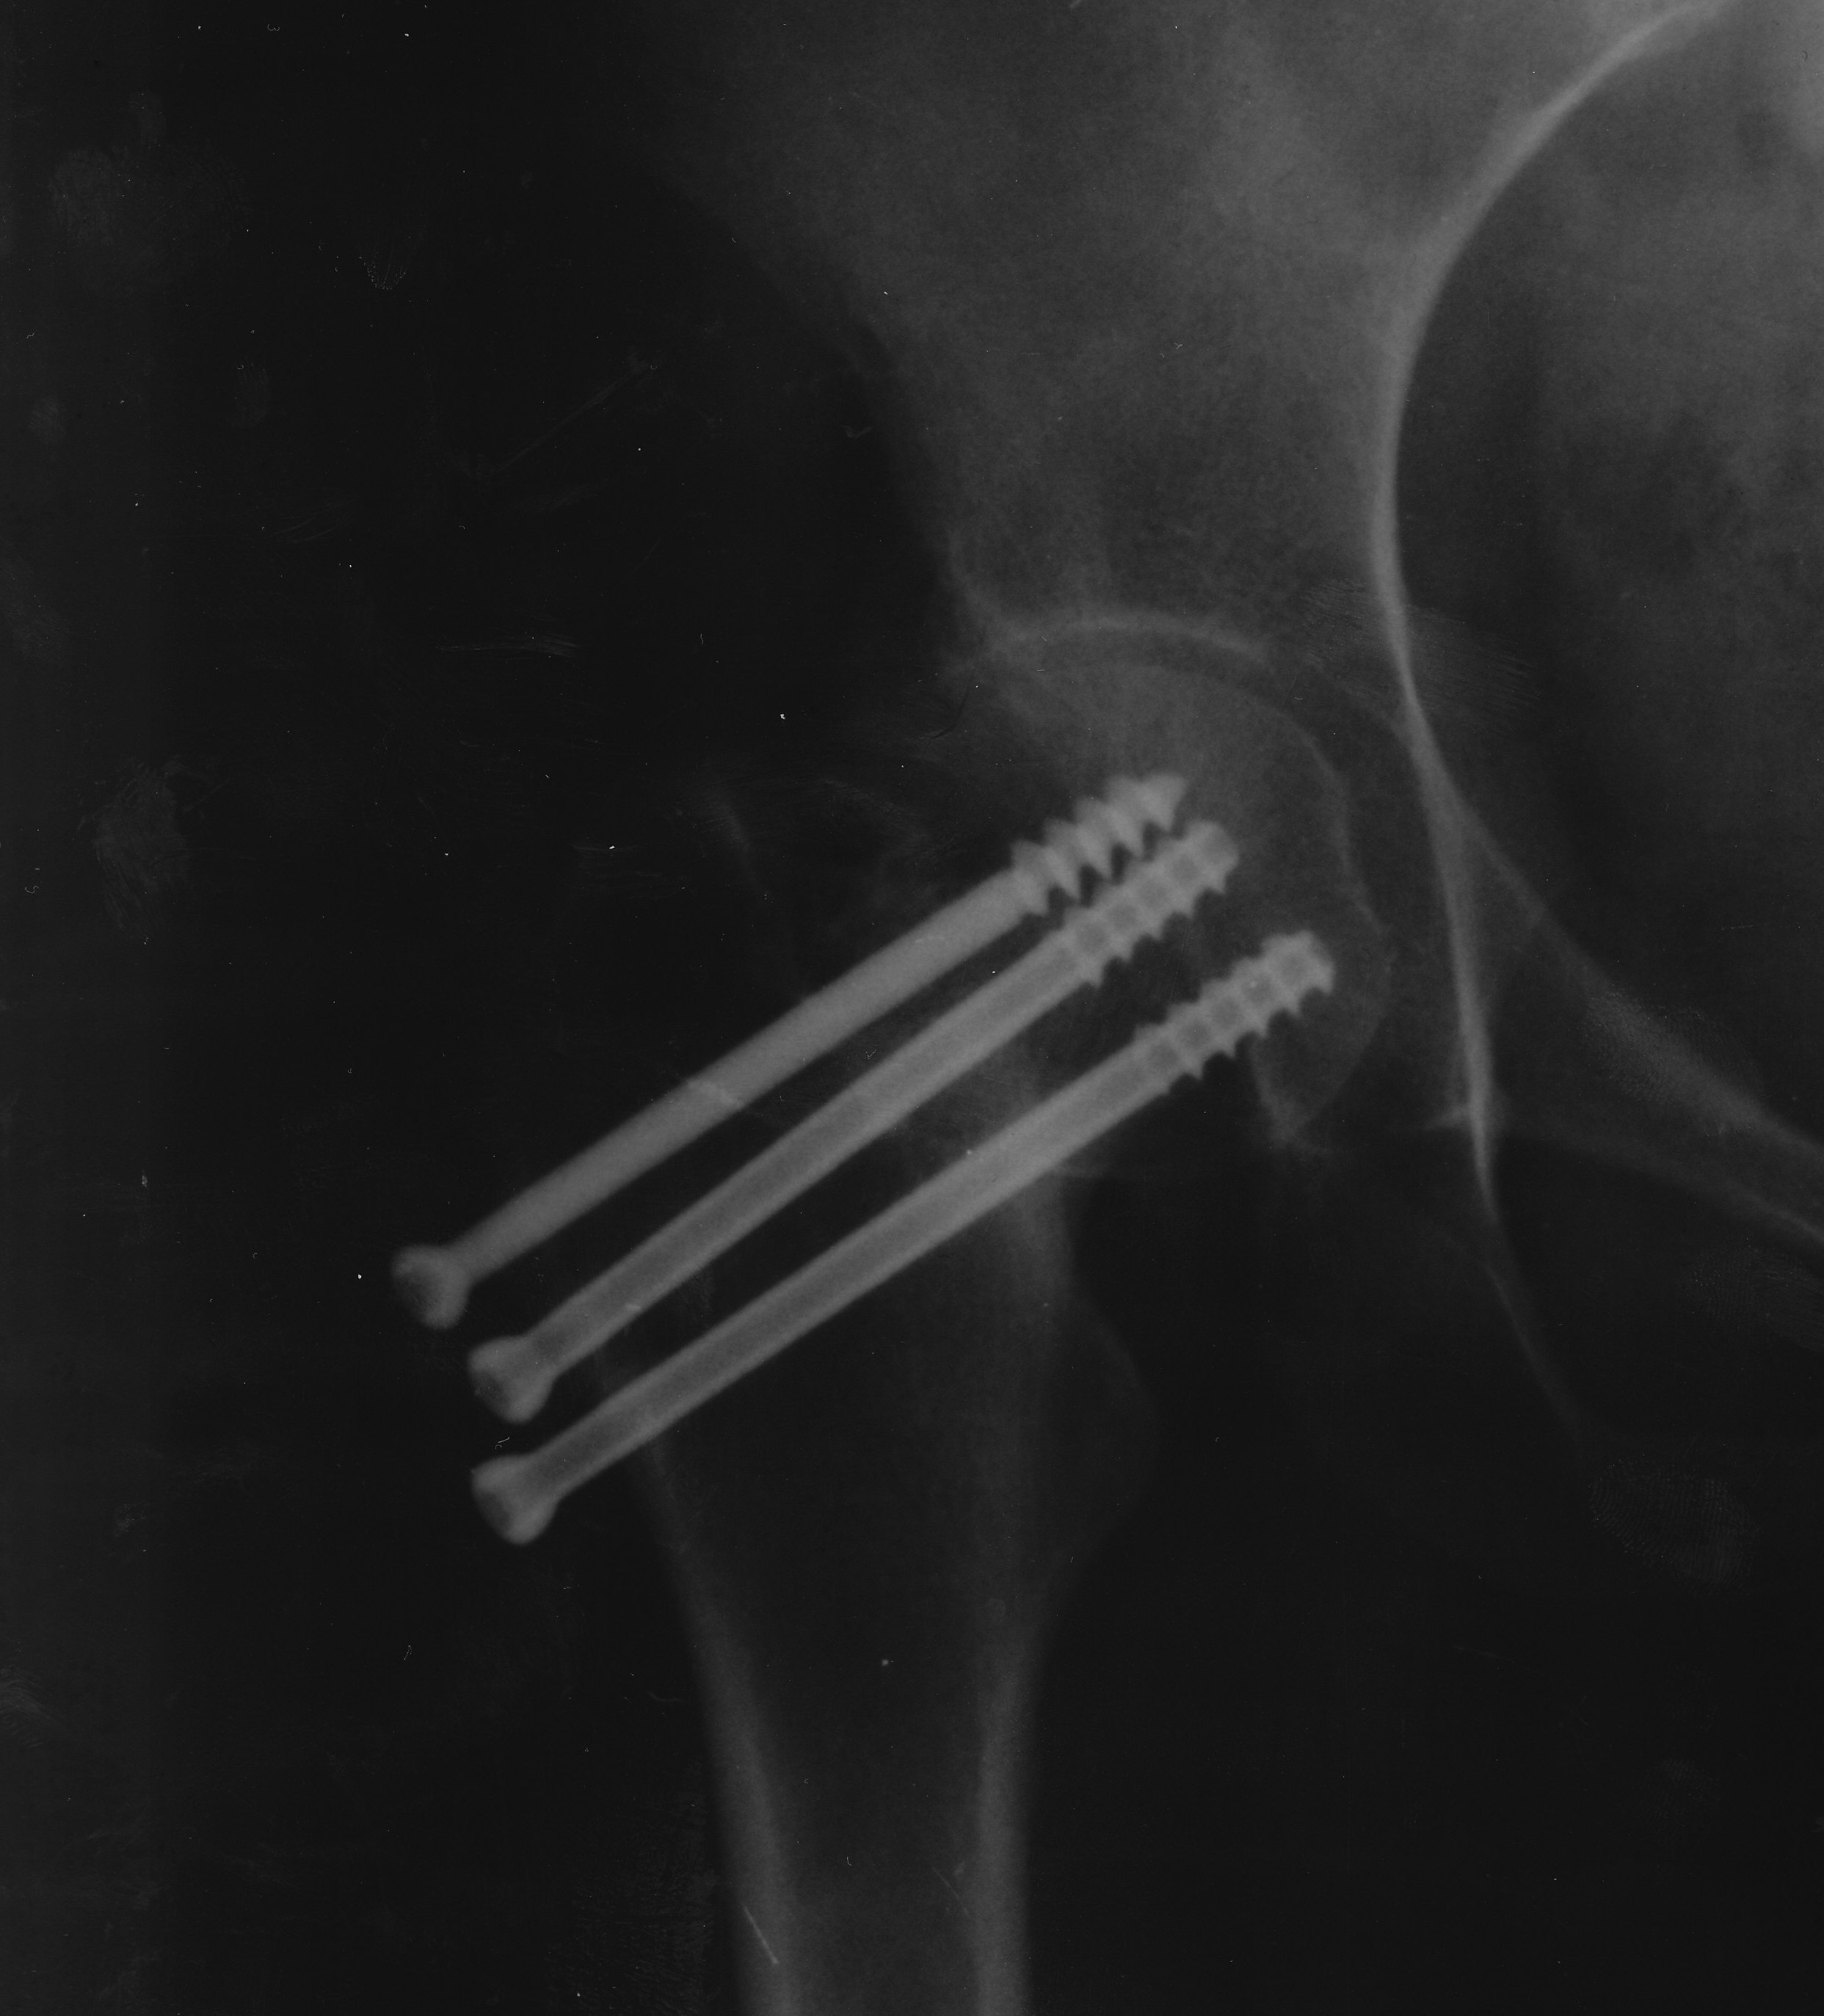

Удачная операция остеосинтеза шейки бедра тремя винтами (оскольчатый перелом, со смещением), пациент ходит , спустя 1 год начали ощущаться боли при различных положениях ноги или при ходьбе, закономерности появления болей не выявленно. При нажатии с со стороны ягодицы в область сустава ощущается небольшая боль. Рентгеновские снимки делались после операции с частотой в два месяца, смещений винтов не выявленно. Нагрузку начали давать с 4 месяцев по 3-5 кг. полная нагрузка началась с 5 месяцев, и после ходьба с палочкой в течении трёх месяцев. Интересуют переодичные боли в области сустава. Повышения температуры в месте сустава отсутствуют.

Забыл уточнить. Пациент, девушка 26 лет. Есть возможность выложить снимки.

Ездили на обследование.

Сделали снимок, визуально всё в норме. Врач сказал что всё нормально, беспокоится не стоит. Из препаратов, посоветовал пить Терафлекс, по инструкции.

Снимки выложу, хотя бы даже с информационной целью.

Дело в данном случае в том, что пациентка нормально ходит, но беспокоят периодичные боли при движении, а также сильная боль при нажатии на поверхность бедра сбоку. Уважаемый доктор, подскажите возможные противовоспалительные и костнорегенерирующие препараты для лечения перелома шейки бедра.

Копия IMG_0005.jpg

478KB (489977 bytes)